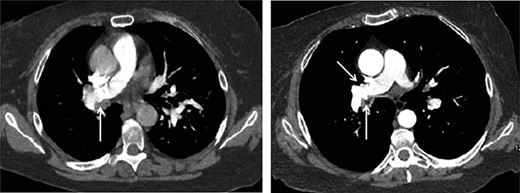

Initially, the patient reported feeling better, however, she then returned to the hospital 6 days later with worsening shortness of breath. Her course was now complicated with hemoptysis and hypoxia. The patient had been on rivaroxaban due to the history of DVT and thrombophilia. The oral anticoagulants were held on admission. A subsequent chest computed tomography demonstrated worsening right-sided pneumonia. There was also evidence of mild-to-moderate pneumopericardium and mild pneumomediastinum, due to small airway barotrauma from persistent coughing. There was a question of pseudoaneurysm of the right pulmonary artery which in retrospect appeared slightly enlarged from 12 days prior (Fig. 1a and b).

(1a) Axial CT chest slice shows small irregularity of right pulmonary artery wall (white arrow) with clot-filled bronchus. (1b) Axial CT chest slice shows increased irregularity of right pulmonary artery wall (white arrow) with open lumen bronchus. Possible opposite side pulmonary artery wall irregularity (yellow arrow).